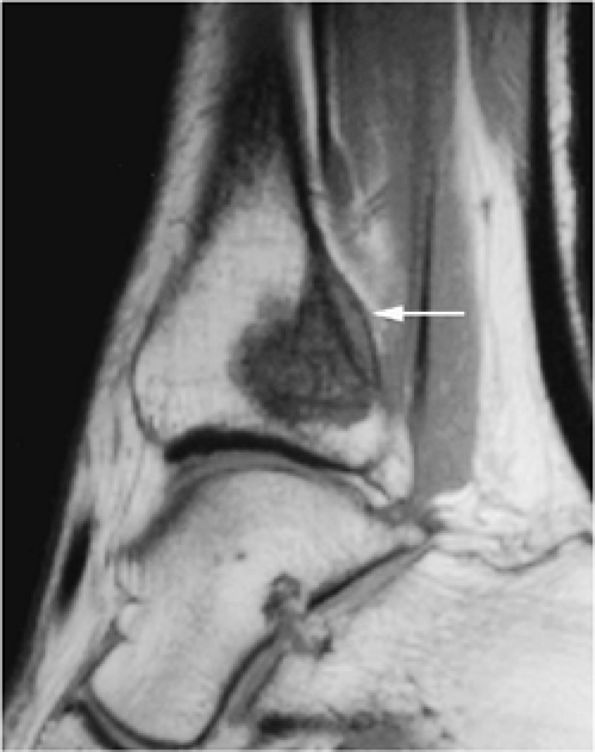

FIGURE 14-2 ● Osteosarcoma of the distal tibia is seen on a sagittal proton density-weighted image. Cortical thinning and periosteal reaction are demonstrated (arrow).